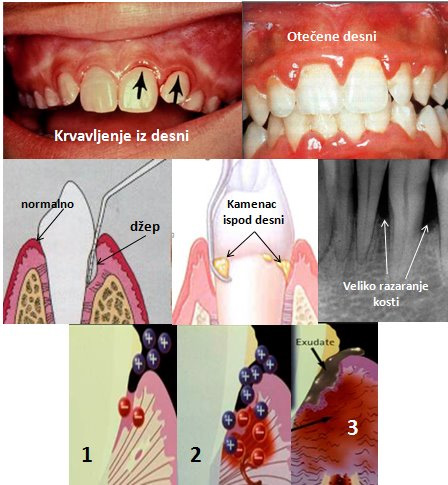

Prvi znaci promena, koji se uglavnom zanemaruju, su krvavljenja prilikom pranja zuba, koršćenja zubnog konca ili čačkalice. Radi se o zapaljenskoj reakciji u desnima koja se stručno naziva GINGIVITIS. Uzrok su bakterije iz usne duplje organizovane u specijalni ekološki sistem nazvan ZUBNI PLAK. U početku se na površini zuba naseljavaju samo bakterije koje koriste vazduh(aerobne bakterije). Ukoliko je prisutna kisela sredina, postoje ugljeni hidrati i ako se u većoj količini prenesu iz usta roditelja(o čemu smo već više puta govorili) to će pre svega biti streptokoke(npr Streptococus mutans) i one izazivaju karijes. Bakterije stvaraju posebne materije od prisutnih šećera koje ih kao cement još više učvrsćuju i povezuju i omogućavaju naseljavanje i drugih vrsta-sazrevanja plaka. U jednom trenutku se stvara sredina u kojoj nema kiseonika i to omogućava razvoj bezvazdušnih bakterija(anaerobi). To se događa ako se zubni plak ne ukljanja redovno sa ivice desni i izmežu zuba. Redovno znači SVAKODNEVNO!

Bakterije stvaraju različite toksine i enzime i oni deluju na sluznicu desni. Prema manjim količinama ovih materija, desni se efikasno brane sprečavajući njihov prodor(DONJI RED SLIKA- 1), ali ako je taj napad dugotrajan i agresivan, probija se barijera sluznice i toksini prodiru u vezivno tkivo ispod epitela. Sledeći nivo odbrane je zapaljenje koje ima za cilj da zaustavi agresora. Znaci zapaljenja su otok, crvenilo i izliv krvi iz malih krvnih sudova. Na epitelu sluznice se javljaju mikromehanička ostećenja i kao posledica svega toga javlja se gore navedeno

KRVAVLJENJE. (DONJI RED SLIKA- 2). Iako je reć o odbrani organizma, čitav niz odbrambenog arsenala vrši i kolateralnu štetu oštećujući i sopstveno tkivo. Kod pojedinih osoba postoji izražena osetljivost u toku bakterijama izazvanog zapaljenja, pojačano se aktiviraju određeni enzimi koji doprinose ubrzanom razaranja sopstvenih vezivnih vlakana, pa i kosti. Na taj način se gubi veza zuba za kost, oni se rasklačuju i posle određenog perioda, ako se ništa ne preduzima i ispadaju.( DONJI RED SLIKA- 3).

Pojava zapaljenja desni dovodi do toga da se one razdavajaju od površine zuba za koje su u uslovima potpunog zdravlja pripojene. U taj prostor prodiru bakterije i stvaraju nove količine zubnog plaka. Gore navedeno razaranje vlakana i kosti još više produbljuje taj prostor i dovodi do daljeg prodiranja plaka prema korenu. Prostor se naziva DŽEP i on može da bude samo u desnima ili već i u koštanom delu.(SREDNJI RED SLIKA). Stomatolog može da izmeri dubinu tog prostora i da proceni da li se radi o džepu ili još uvek normalnom stanju. To je jako bitno, jer kada imamo DŽEP i pored idealnog pranja zuba nije moguće ukloniti zubni plak iz njega, tako da je njegovo dejstvo pojačano i ubrzano. Tada je već potrebna profesionalna pomoć. Ukoliko je džep previše dubok mora se uraditi i hiruška intervencija da se on ukloni i da seobezbedi normalno prijanjanje desni uz zub. Ali, ako se i dalje ne održava pravilna i redovna oralna higijena i tako sprečava sazrevanje plaka, džep će se opet razviti.

U formiranom džepu deo zubnog plaka može da mineralizuje i tako nastaju mali kamenčići koji se nazivaju KONKREMENTI.(SREDNJI RED SLIKA) Njih treba razlikovati od KAMENCA koji je vidljiv spolja i nastaje mineralizacijom zubnog plaka. I sam kamenac je štetan jer pritiska i mehanički oštećuje sluznicu desni i pomaže prodor toksina jer se na njegovoj površini nalaze sveže naslage bakterija. Ali jako je važno ne samo da se ultrazvukom ukloni vidljivi kamenac, već da se otkriju i uklone i konkrementi i time omogući uklanjanje džepa.